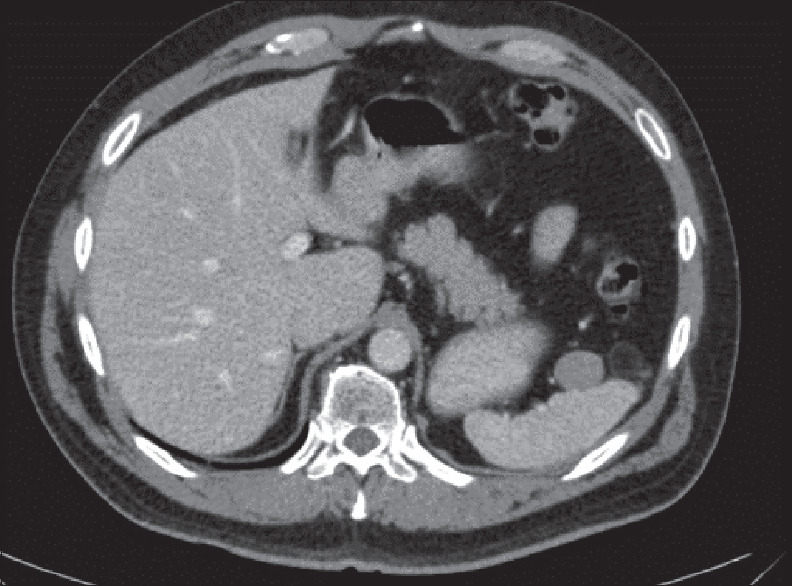

硬纤维瘤,也称为硬纤维瘤,是一种良性的浸润性肿瘤,常出现在既往手术部位旁边。腹内肿瘤通常累及肠系膜,但脾门少见。我们报告一例经腹腔镜切除的脾门硬纤维瘤,患者为70岁男性,既往有嫌色性肾细胞癌及眼梭形黑色素瘤病史。虽然是良性的,但硬纤维瘤可能是浸润性的,并产生严重的并发症。治疗方法仍然存在争议,从手术和药物治疗到观察。考虑到并发症和复发的风险,DTF的治疗必须个体化。

Desmoid-type fibromatoses (DTFs), also known as desmoid tumors, are benign but infiltrative neoplasms that often appear next to previous surgical site. Intra-abdominal tumors usually involve the mesentery, but splenic hilum is an unusual localization. We present a case of a desmoid tumor of the splenic hilum laparoscopically resected in a 70-year-old male with a previous history of chromophobe renal cell carcinoma and ocular spindle melanoma. Although benign, desmoid tumors might be infiltrative and produce serious complications. Treatment remains controversial, ranging from surgery and medical therapies to observation. Management of DTF must be individualized, considering the risk of complications and recurrence.